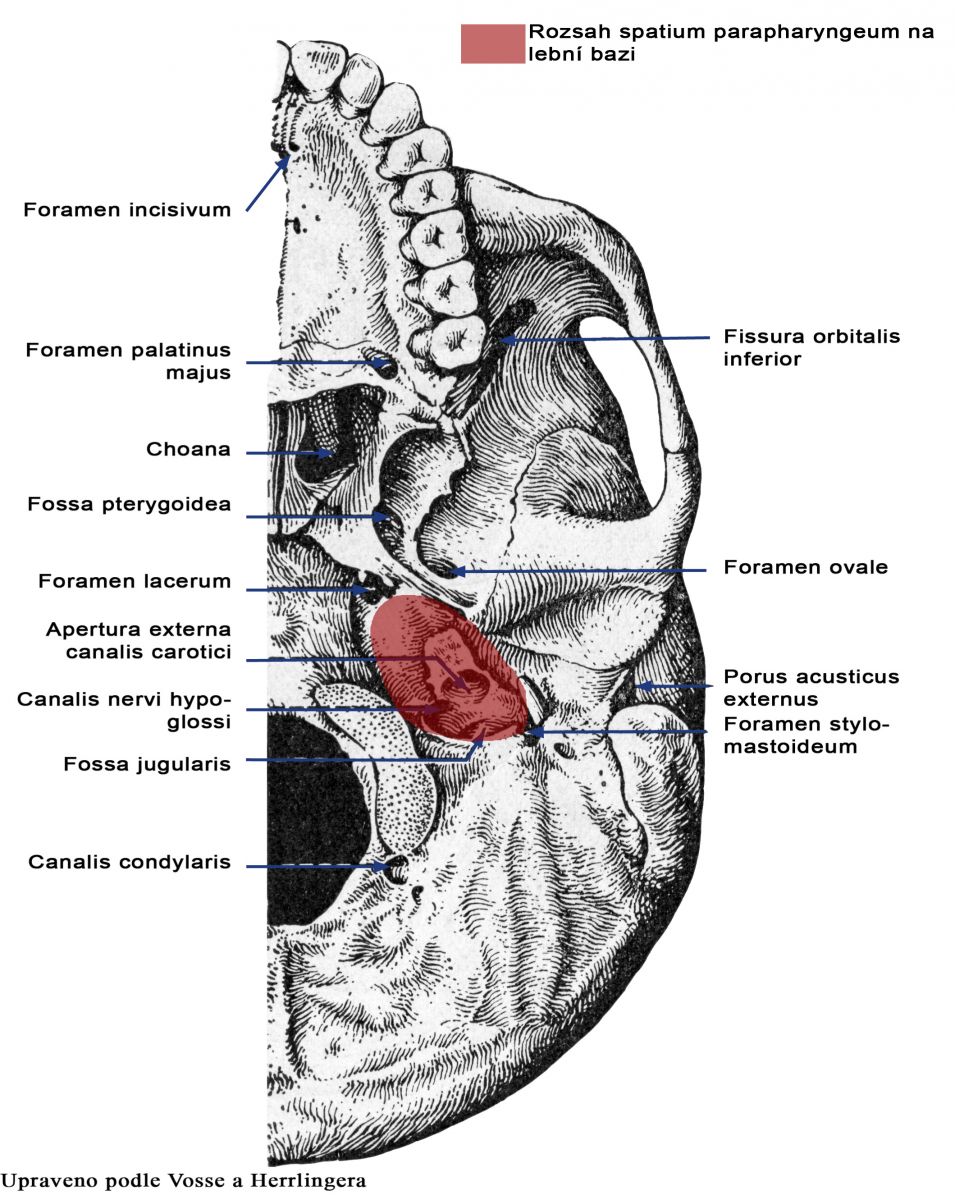

Анатомические детали: Фотографии топографии черепа с нижнего вида